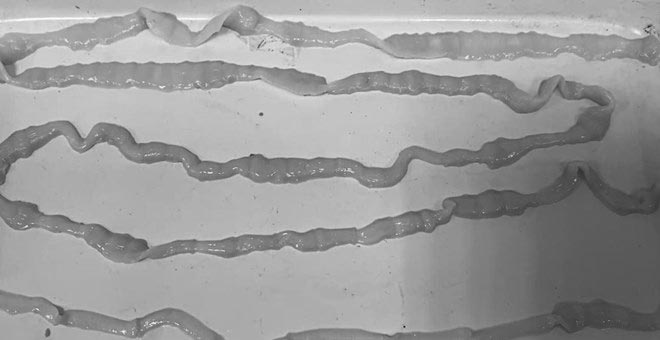

彼が検査とMRIのために病院に行ったとき、医師は彼の脳に無数の嚢胞があることを発見しました。原因は、安全でない食習慣、特に春巻き、肉サラダ、魚、生野菜であることが判明しました。たとえきれいに処理したと思っていたとしても、患者は、ブタ条虫の幼虫が静かに体内に入り、血流を通って脳に到達し、そこに「巣」を作ったことが信じられなかった。

脳虫症の最も危険で持続的な後遺症の 1 つは、治療後でも条虫嚢胞が完全に消失せず、石灰化して脳内に「石灰化」を形成することです。これらの石灰化は永続的であり、将来的には炎症の焦点となり、発作やてんかんを引き起こす可能性があります。